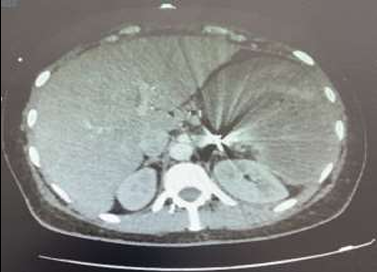

Un scanner abdomino-pelvien (TDM) a été réalisé en urgence, révélant :

-

Un hémopéritoine sur une fracture splénique de grade III selon la classification AAST.

-

Un hématome intraparenchymateux mesurant entre 105 et 89 mm.

-

Un hématome sous-capsulaire.

-

Un hémopéritoine d’abondance modérée, sans saignement actif visible (Figure 1).

Figure 1 : Scanner abdominal avec injection, coupe axiale : rupture d’un hématome sous-capsulaire splénique et hémopéritoine (Grade AAST 3).